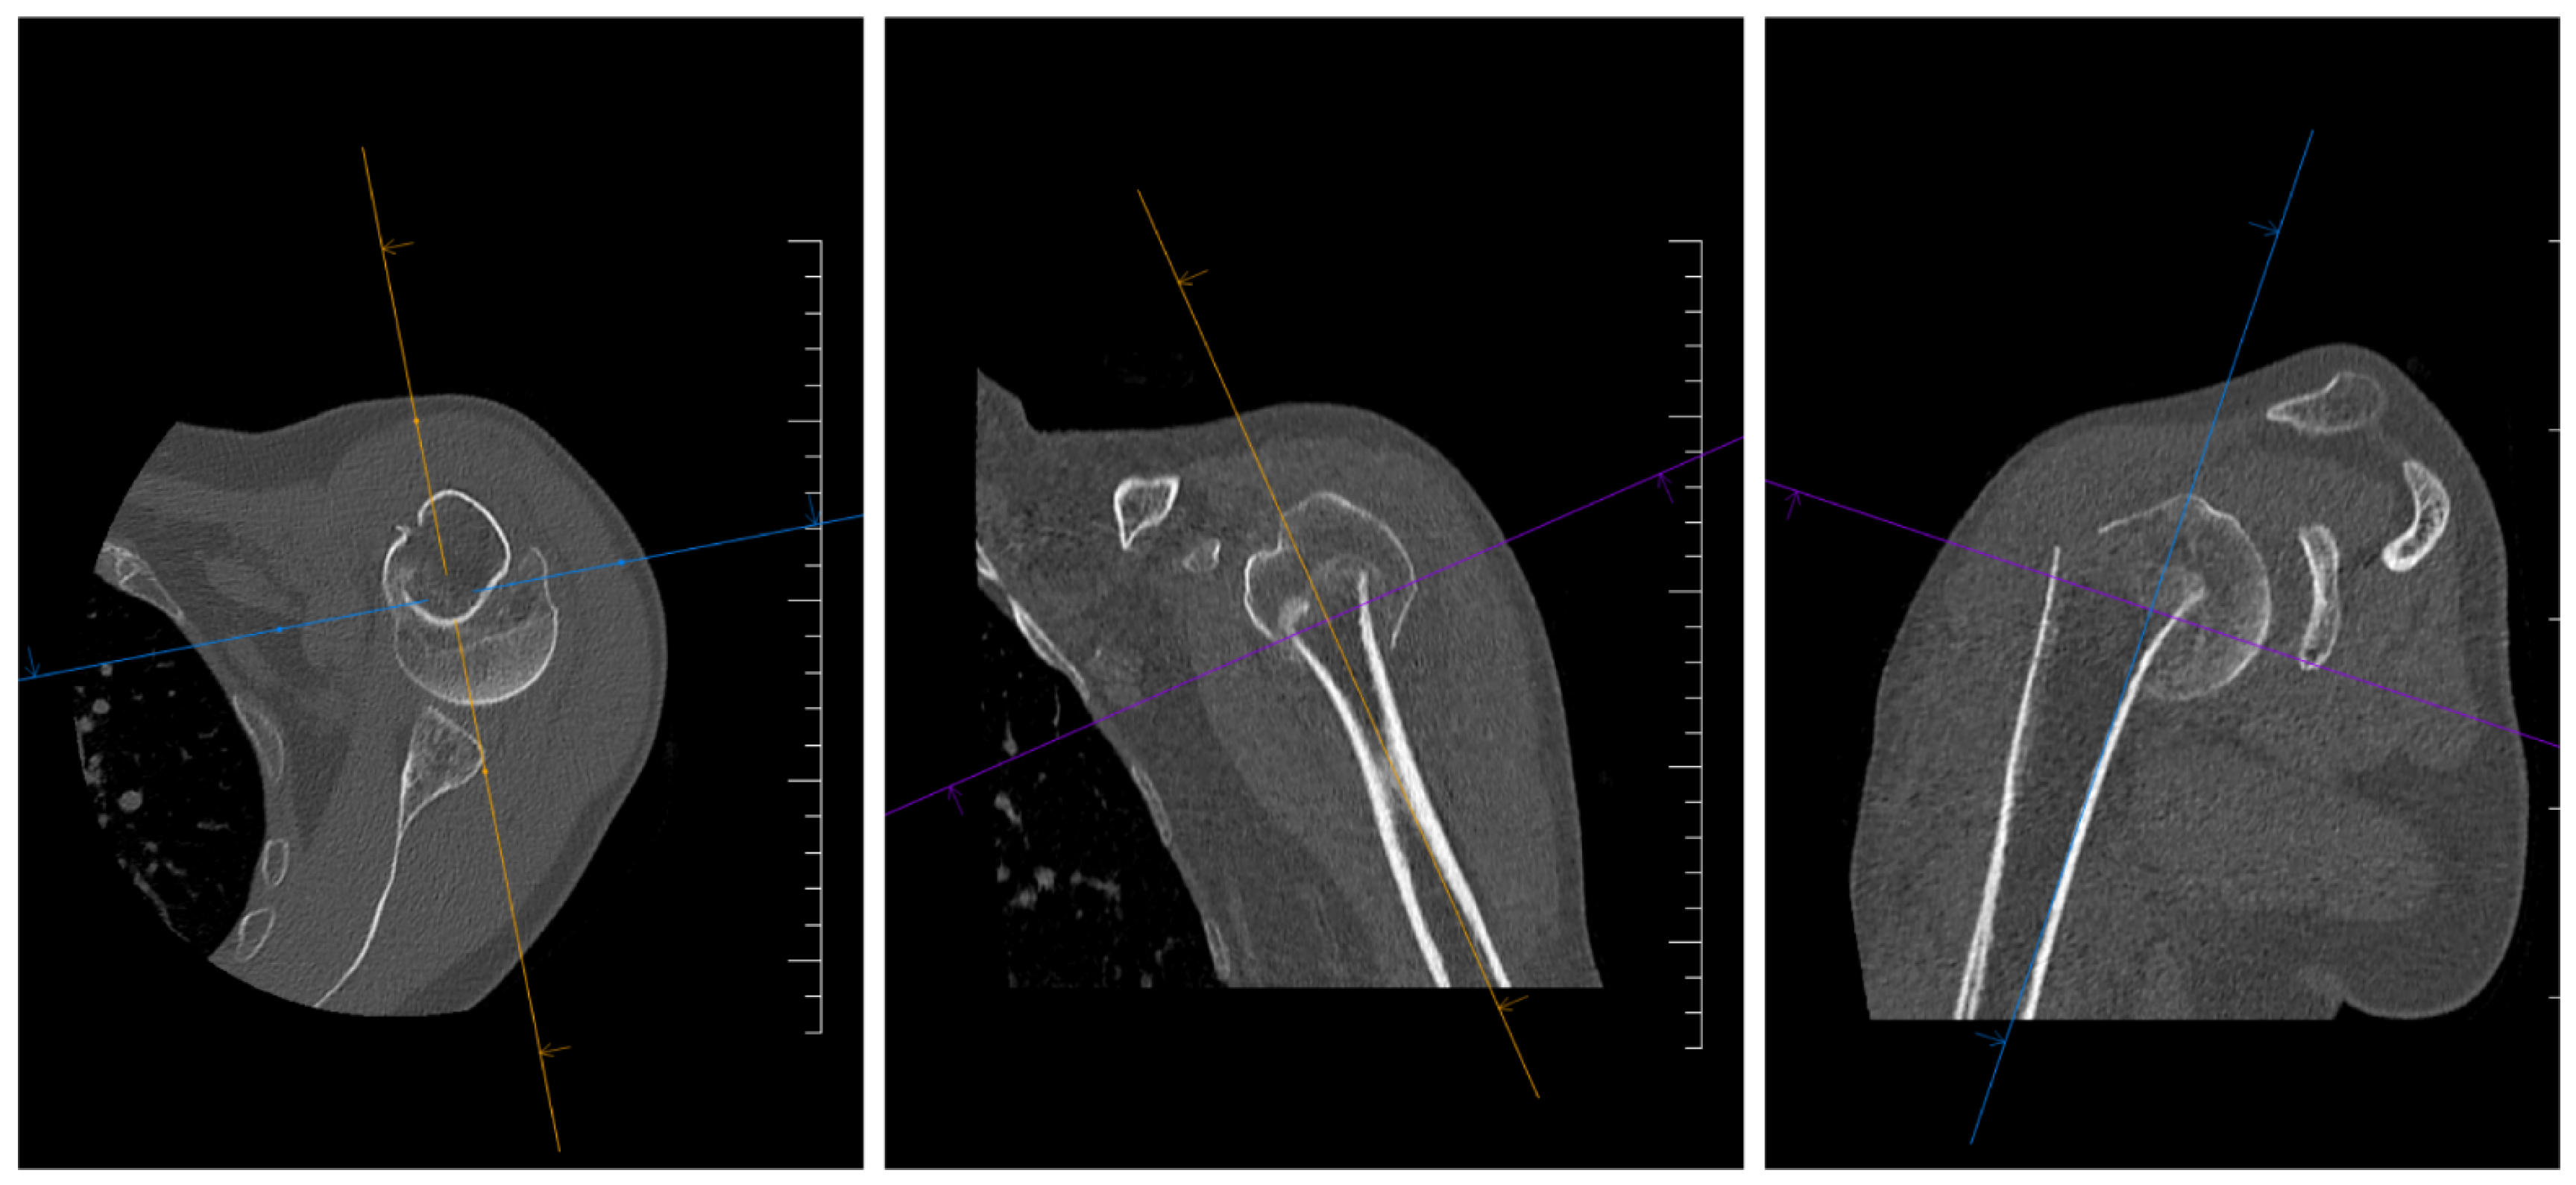

2. Materials and Methods